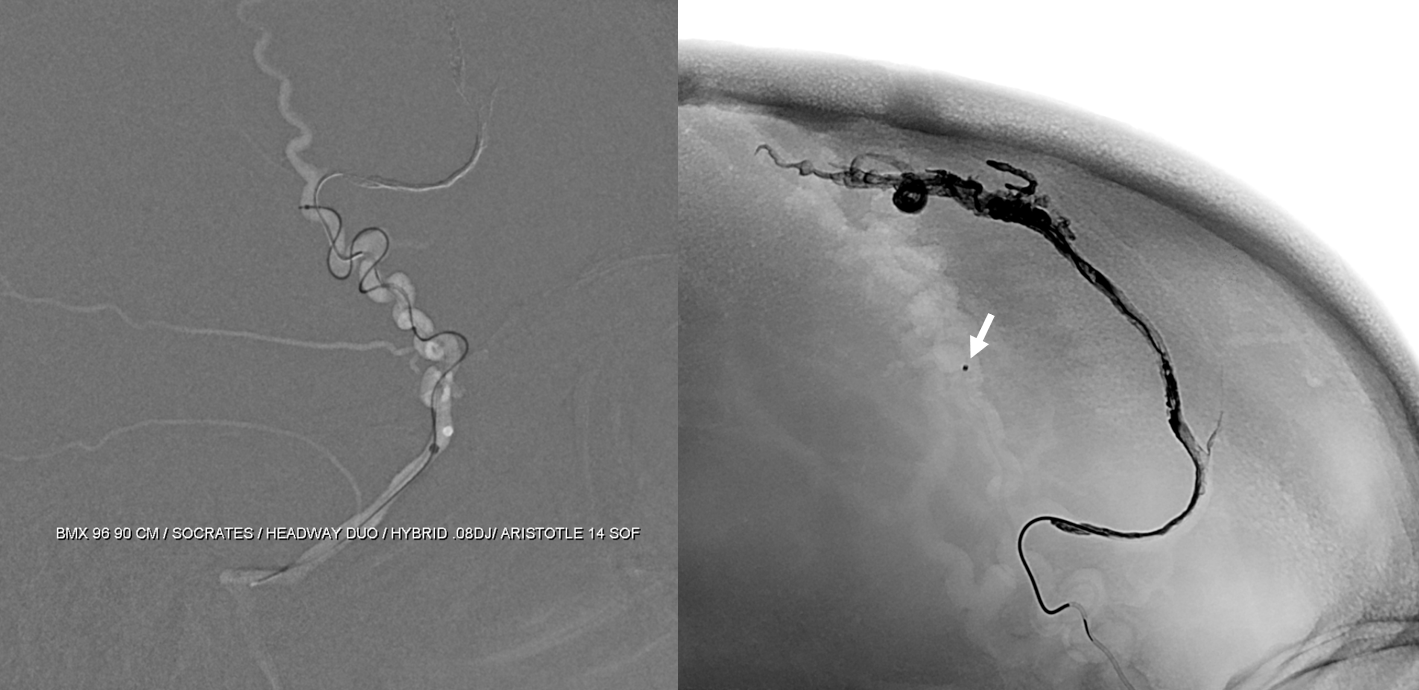

This shows the mistake. Can u see?

nBCA — its not that Onyx or nBCA is better. From this position Onyx will not reach for sure so nBCA is the way to go

Glue reflux

Now, look at the images below and tell me what the mistake during first injection was. The images on right should read post embo 1